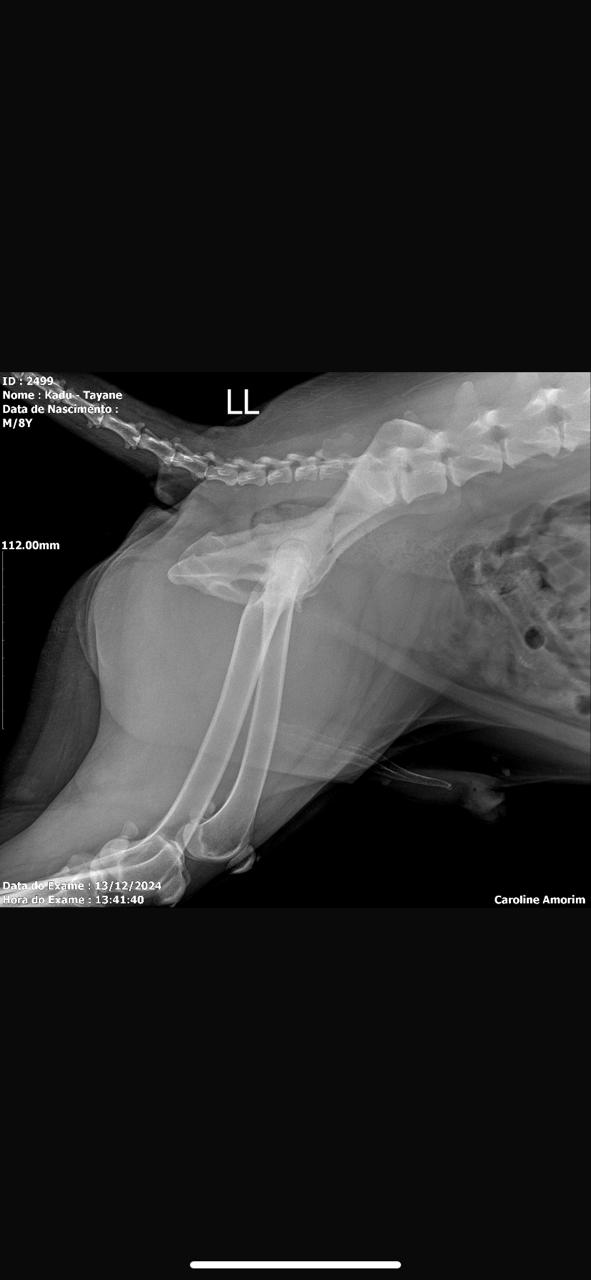

Displasia coxofemoral, que é uma doença que afeta a articulação do quadril do animal, causando dificuldade de se movimentar (andar, saltar, levantar) e degeneração articular.

Protrusões nos discos da coluna vertebral, o que está causando MUITA dor a ele 😕